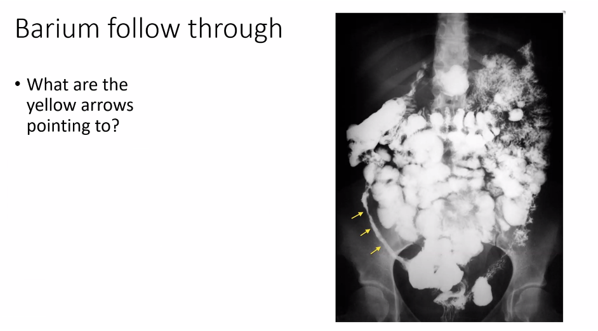

Yellow arrow – stricture – caecum and ascending colon is very narrow – dye is hardly making way through. Lumen very narrow.

Confirm the dx of crohn’s disease

Small bowel – barium filling and distending the bowel